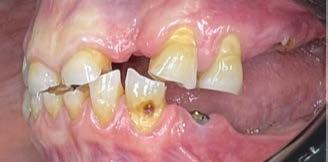

Exploración Intraoral

Presenta un estado oral deficitario. Parcialmente edéntula, con colapso de mordida, migración dental patológica, restauraciones de resina antiguas fisuradas y filtradas, transparencia y exposición de cámara pulpar secundaria a desgastes con pérdida de estructura e integridad de tejido dental importante (Figuras 1 a 4). Portadora a tiempo parcial de prótesis removibles desadaptadas de más de 10 años de antigüedad, refiriendo incapacidad de adaptación a este tipo de prótesis.

Exploración extraoral

Se constata reducción del tercio facial inferior produciendo a nivel estético una apariencia envejecida por formación de surcos en las comisuras labiales («líneas de marioneta») secundarias a una disminución de la dimensión vertical por desgaste dental (Figuras 5 y 6).

Exploración radiológica

Mediante CBCT constatamos atrofias óseas severas y disminución de soporte óseo periodontal en relación con las piezas dentales.